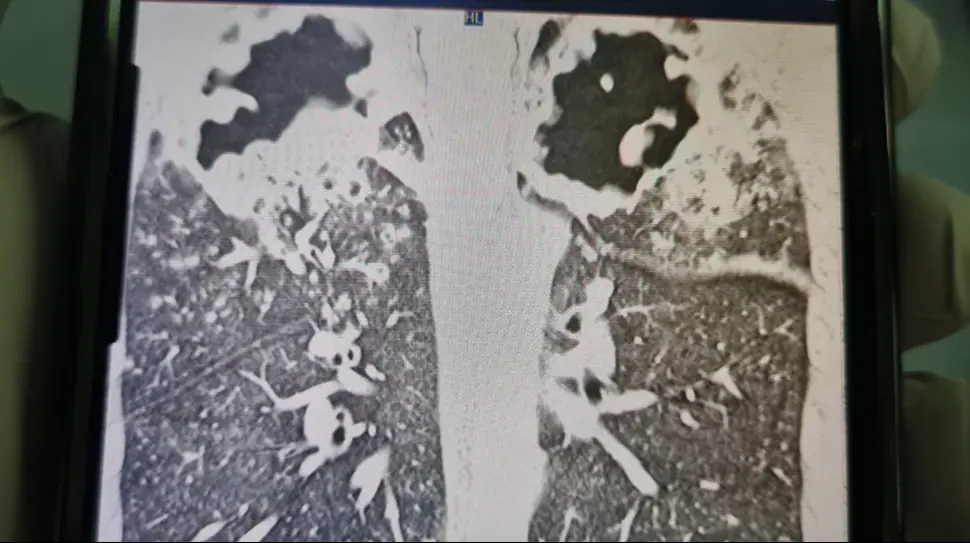

An X-Ray shows holes in Capper's lungs. Credit: GoFundMe

Before his diagnosis, an X-ray revealed a hole in Capper's lungs, and within just six weeks, the infection had consumed a third of his lung tissue.